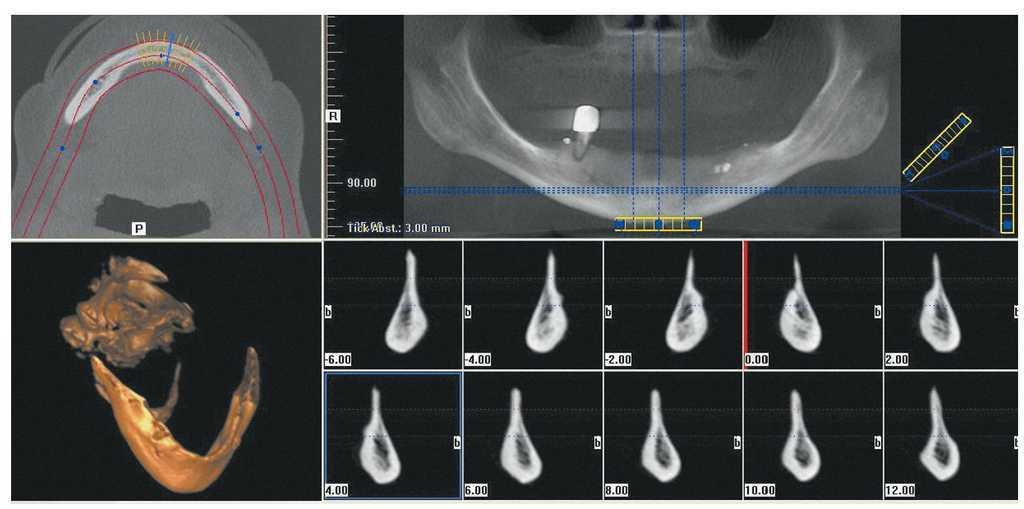

Los métodos de diagnóstico de la consulta dental y una cuidadosa anamnesis del paciente son suficientes para determinar la existencia de uno de los factores mencionados que desaconsejan realizar el tratamiento con implantes en la consulta dental general. Las radiografías intraorales y las radiografías panorámicas son métodos de diagnóstico por imagen ampliamente utilizados en la consulta general. Estos procedimientos pueden combinarse con dispositivos de medición radiográfica integrados que permiten determinar los factores de ampliación y calcular con precisión las condiciones anatómicas verticales del maxilar y la mandíbula. Con el montaje arbitrario de los modelos, la medición del grosor de la mucosa y el segueteado es posible determinar de forma aproximada la dimensión del hueso en sentido horizontal (fig. 2). Este diagnóstico básico es suficiente en pacientes cuya anamnesis no ha arrojado datos reseñables y con una situación correcta del lecho óseo. En cuanto a la realización de diagnósticos por imagen más exhaustivos, la introducción de la tomografía volumétrica digital ha hecho que la radiología dental se adentrara en una dimensión completamente nueva. Dado que este sistema implica una exposición a la radiación mucho menor que la tomografía computarizada helicoidal clásica, es preferible utilizarlo como método de diagnóstico complementario en presencia de relaciones intermaxilares complejas17,21 (fig. 3).

Figura 3. Ventanas de visualización para evaluar las imágenes 3D en la tomografía volumétrica digital. Arriba izquierda: corte axial del maxilar inferior; arriba derecha: reconstrucción panorámica; abajo izquierda: reproducción en 3D; abajo derecha: reconstrucción de la sección transversal de la mandíbula.